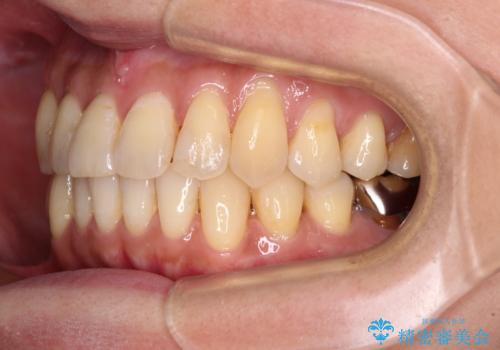

- 前歯のクロスバイトが気になり、インビザラインによる矯正治療を希望して来院された患者様です。

上顎側切歯(上の真ん中から2番目の歯)が舌側転位している場合、インビザラインでは仕上げきれないことが多く、更には無理して動かそうとすると歯髄壊死を起こすリスクが高いと言われています。

インビザラインで歯列を移動する前に、上顎前歯をワイヤー矯正で整え、その後上下歯列をインビザラインにて矯正治療を行うこととしました。

舌側転位している側切歯特有の、切縁の位置が不揃いであったり、根元が内側に引っ込んだ状態であったりという、インビザライン独特の仕上がりになることなく、きれいに整った歯列とすることができました。